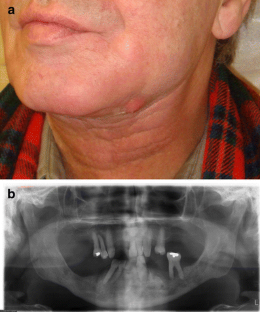

Fig. 1

Fig. 2